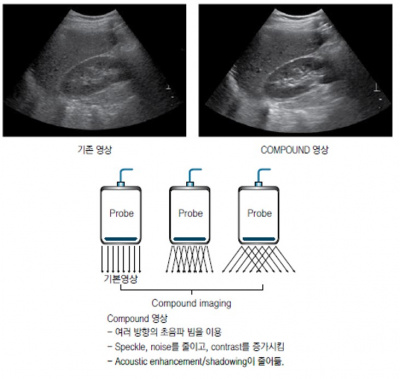

추가적인 영상 조절 ④ : Spatial compound imaging

한 방향의 초음파 빔을 사용하는 기존 초음파 영상과 달리 여러 방향의 초음파 빔을 이용하여 얻은 에코를 병합 평균화하여 얻는 영상을 compound image라고 한다. 따라서 작은 조직의 산란으로 인한 speckle이나 noise를 줄이고, contrast를 높이며 조직 간의 경계 면을 선명하게 해준다. 하지만 Acoustic enhancement 및 shadowing artifact 같은 유용한 정보가 줄어든다.

초음파 검사 장비의 기본구조 18.jpg